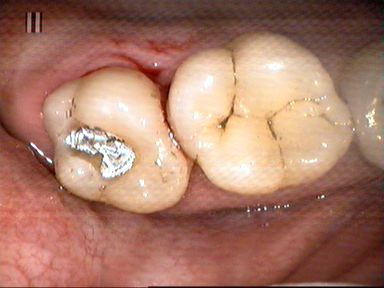

Leczenie próchnicy wtórnej ostatniego górnego trzonowca. Ze względu na trudny dostęp ząb odbudowano laboratoryjnie wykonanym wkładem kompozytowym.